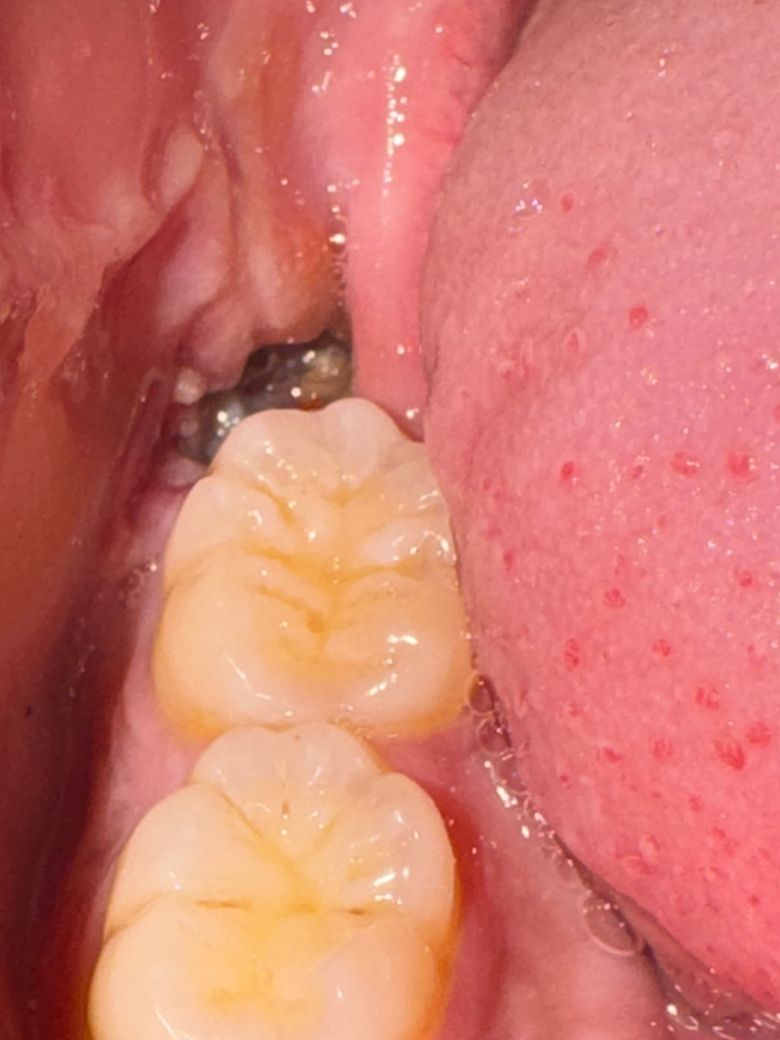

사랑니 발치후에 약3일이 지났는데 정상적인 상태인지 드라이소켓 전조인지 모르겠습니다

3일정도 지났는데 일단 구멍자체는 좀 좁아졌거든요. 그런데 이게 지금 정상적으로 치유가 되고 있는지 의문이라 이렇게 글 남깁니다. 내부가 깔끔하지 않고 뭔가 이상한게 있는데 정상인가요? 그리고 통증이 있기는 한데 막 너무 심한 통증은 아니고 은은하고 약한 통증이 있습니다. 따로 악취가 동반되지는 않고 있구요.

발치와 내 다량의 식편 껴있는 것으로 보이며 물양치를 통해 헹궈내시거나 치과 내원하셔서 드레싱 받으시기를 바랍니다. 음식물 많이 껴있으면 치유 부전 생기며 감염될 수 있으니 꼭 잘 헹궈내시기 바랍니다.

사진상 발치부위는 특별히 이상이 있어보이진 않습니다 치유과정 중에 생기는 염증,육아조직으로 보입니다